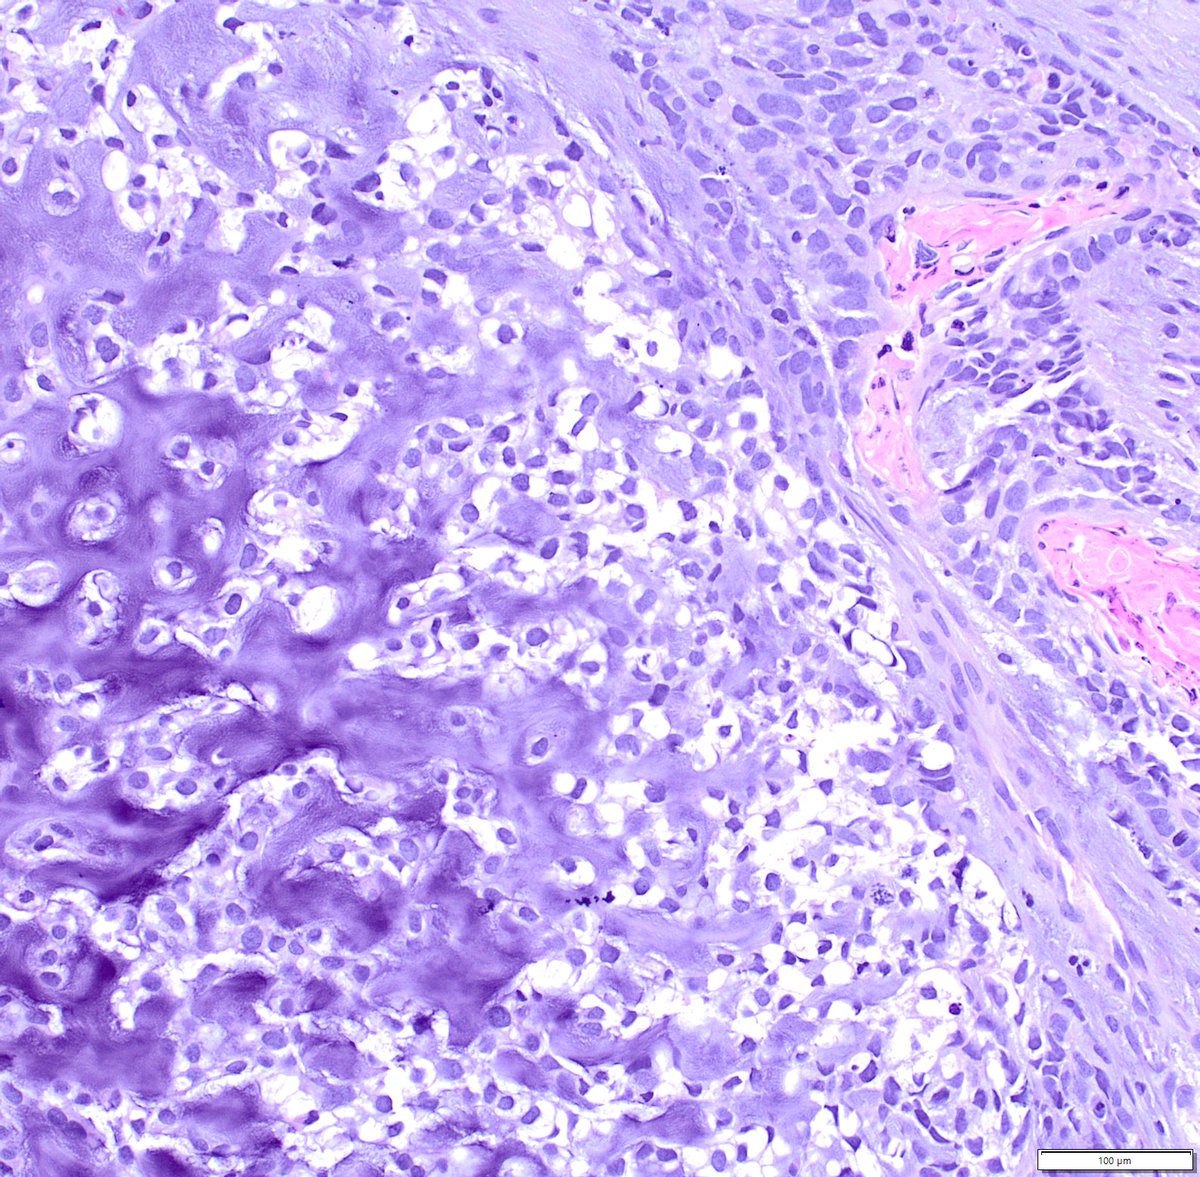

Just out in AJSP – a paper from our group describing a MAJOR new oddity. Tumors that normally arise in the jaw from tooth🦷precursors (ameloblastoma) – but as lung primaries 🫁! This was a neat collaboration b/w MSKCC, Mayo and UTSW where these cases were encountered independently, and we put our heads together with the help of original contributors and fellows to tackle this puzzle. Time will tell if these are truly exceptional or have been underrecognized. journals.lww.com/ajsp/fulltext/… @JLHornick @ENTpathology @MSKPathology @PulmPathSoc @yro854 @thoracicpath @Path_Matt @SansanoValero @AndreMo77438628